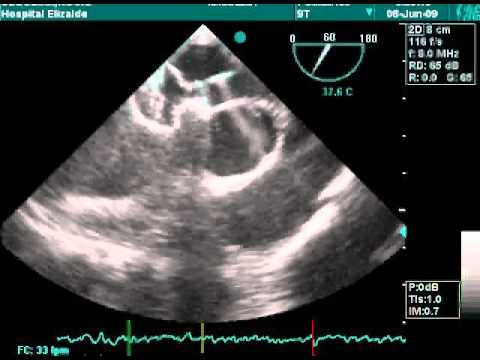

Transcatheter Closure - Movie 3: ASD TEE echo

Transcatheter Closure - Movie 7: Pull and push on echo